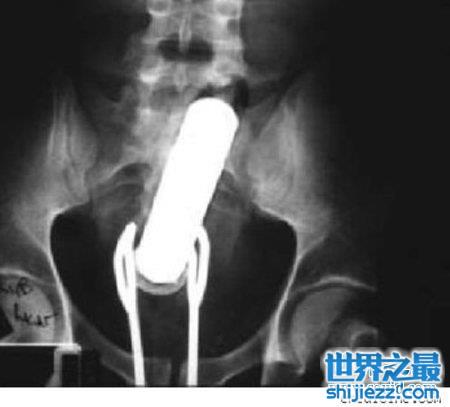

3、炮弹

这是个凄凉的故事,伦敦的一位二战老兵被痔疮折磨着,于是他就把一发炮弹把痔疮塞进了菊花中。结果有一天他不小心塞的太猛了,于是炮弹就困在里面了。呃……因为这是真正的炮弹,所以当他求医的时候,拆弹小组也来到医院协助拆弹。